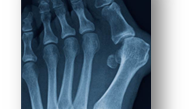

Вы знаете, на самом-то деле “косточка” не растет. Шишка на большом пальце - это не нарост или отложение солей, а деформация сустава, которая и образует “косточку” у основания большого пальца. Давайте разберемся, какие изменения происходят в стопе и образуют “шишку” или “косточку” и почему она в 10 раз чаще бывает у женщин? “Косточка” у большого пальца на медицинском языке называется Hallux Valgus. Это распространенная деформация, которая с возрастом встречается все чаще и чаще: В норме при ходьбе у человека на I головку первой плюсневой кости и первый палец приходится 50% нагрузки...

Появление шишки на большом пальце ноги не только портит внешний вид, но и вызывает физическое дискомфорт. Ортопед Дарья Черемисова объяснила радио Sputnik причины этого явления и как его предотвратить. Эта косточка, известная как вальгусная деформация первого пальца стопы, может привести к артрозу, если не обратить на нее внимание своевременно. Появление шишки связано с деформацией пальца и воспалительным процессом в суставе, который приводит к образованию костного нароста. Необходимо обращаться к врачу при первых признаках изменений, поскольку боль может возникнуть не сразу...